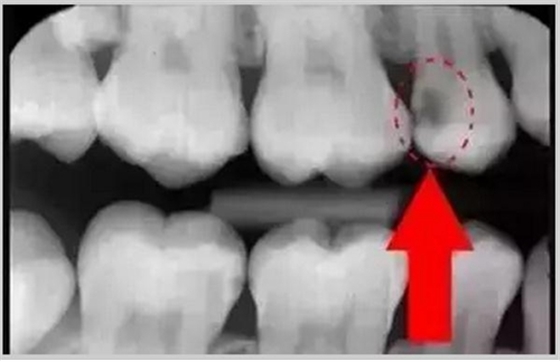

暗的部位說明齲齒已經(jīng)非常嚴(yán)重了!

上面這個(gè)是接近牙髓了!